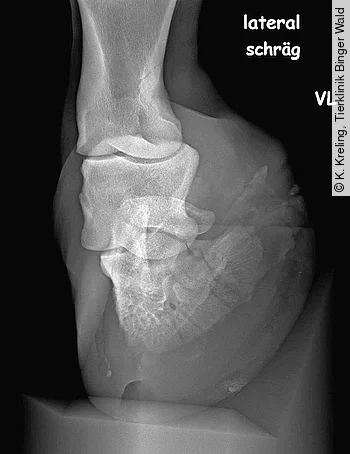

Röntgen

Eine lateromediale und eine schräge Oxspring-Aufnahme führen oft schon zur Diagnose. Der Huf sollte zuvor sehr gründlich gesäubert und ausgeschnitten werden, um Artefakte auf dem Röntgenbild zu vermeiden. Vor allem die Strahlfurchen und Eckstreben sollten mit luftdichtem Material ausgestopft werden, um Luftartefakte in diesen Bereichen zu vermeiden. Die meisten Hufbeinastfrakturen mit Gelenkbeteiligung können in den schrägen Oxspring-Aufnahmen erkannt werden (Abb. 6). Frakturen ohne Gelenkbeteiligung sind dagegen eher in der lateromedialen Aufnahme zu sehen.